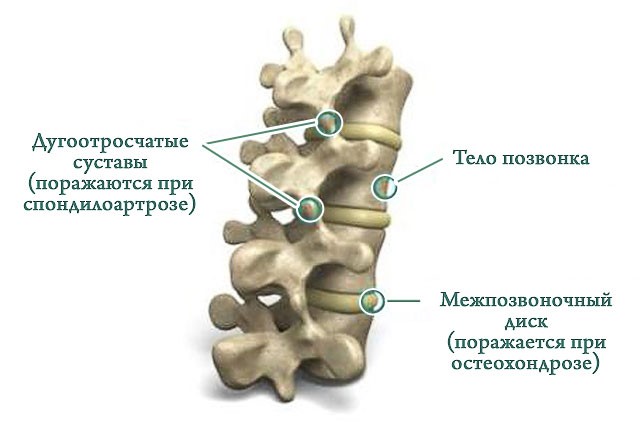

Остеоартрит фасеточных суставов: медицинские снимки и схемы